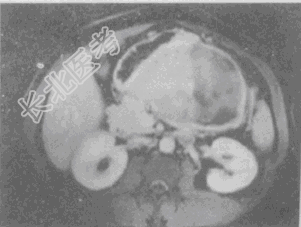

- 单项选择题男,36岁, 腹胀、消化不良、消瘦、中上腹痛,影像检查如下图, 最可能的诊断是

A、胃间质肉瘤并肝转移

B、胃间质瘤并原发性肝癌

C、内胚窦瘤肝转移

D、胃淋巴瘤伴原发性肝癌

E、胃间质瘤并肝血管瘤